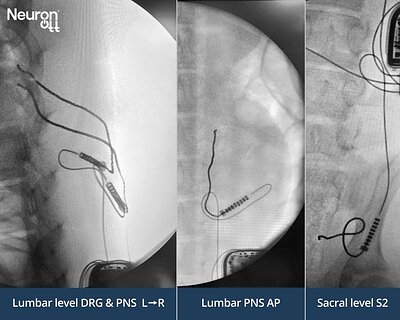

Neuronoff's Injectrode Aims to Revolutionize Neuromodulation